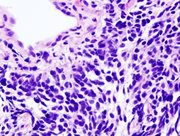

Small cell lung carcinoma (SCLC, also called "oat cell carcinoma") is less common. It tends to arise in the larger airways (primary and secondary bronchi) and grows rapidly, becoming quite large. The "oat" cell contains dense neurosecretory granules ( vesicles containing neuroendocrine hormones) which give this an endocrine/paraneoplastic syndrome association. While initially more sensitive to chemotherapy, it ultimately carries a worse prognosis and is often metastatic at presentation. Small cell lung cancers are divided into Limited stage and Extensive stage disease. This type of lung cancer is strongly associated with smoking.